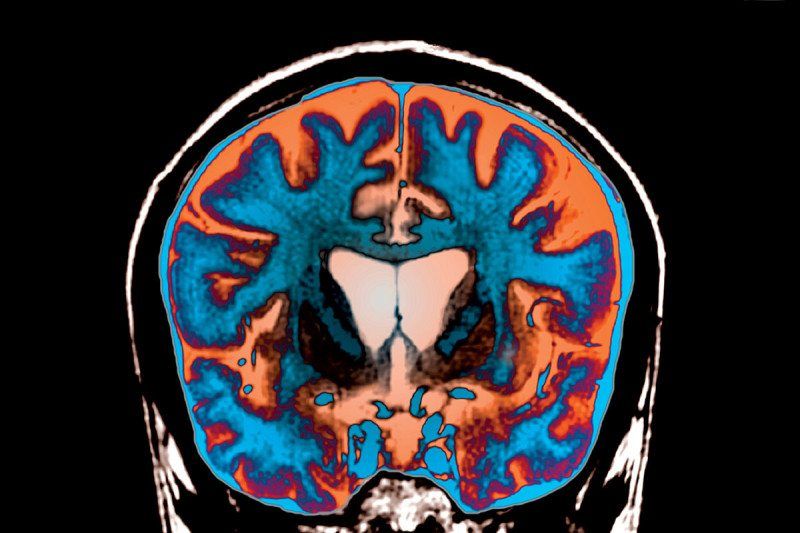

Браун и коллеги провели эксперимент с участием 15 методических актеров, большинство из которых были студентами театральных учебных заведений. Им дали роли Ромео или Джульетты из известной пьесы Уильяма Шекспира. Будучи в образе, актеры отвечали на различные вопросы. Затем их пригласили в лабораторию, где активность их мозга была отсканирована в рамках серии экспериментов.

К примеру, поместив актеров в МРТ, их просили думать над ответами к вопросам, которые появлялись на экране. При этом вопросы были частично связаны с их персонажами. К примеру, их спрашивали: «Пришли бы вы на вечеринку незваным? Сказали бы вы родителям, что влюблены?». Во время эксперимента каждого актера просили отвечать на подобные вопросы в четырех различных ролях в случайном порядке. На один вопрос их просили ответить от своего имени, на другое им надо было ответить так, как ответил бы близкий друг, а еще на один вопрос надо было ответить как Ромео или Джульетта. Еще одна роль предусматривала, что актерам-канадцам нужно было ответить на вопросы от своего имени, но не с канадским, а с британским акцентом.

Исследование показало, что активность мозга отличалась в зависимости от заданных ролей. Когда нужно было отвечать от имени друга, возникало сокращение активности в префронтальной коре, отвечающей за суждение. Эти изменения похожи на результаты предыдущих экспериментов по исследованию «теории разума» или способности делать выводы о гипотетическом мнении или чувствах других людей.

Когда актеры отвечали, будучи в роли, команда обнаружила такие же изменения. Это указывало на то, что во время игры люди используют знание или суждение о третьих лицах – персонажах. Однако, при этом сокращение активности происходило и в двух других регионах мозга префронтальной коры, связанной с самосознанием. Активность была значительно меньше, чем когда актеры отвечали от собственного имени.

Только, когда ответы давали Ромео или Джульетта, в мозге актеров наблюдалось усиление активности в части под названием precuneus, которая связана с сознанием и вниманием.